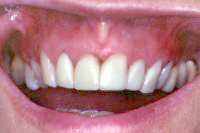

Ein 31 Jahre alter Patient zeigt einen starke Zahnfleisch-Rückgang im Oberkiefer (Abb. 1 und 3) und wir beschliessen, diese Rezessionen zu behandeln.

Der Erfolg der Behandlung ist deutlich in den Abb. 2 und 4 zu sehen. Sehr augenfällig konnte die Situation um den Eckzahn im linken Oberkiefer verbessert werden (vergleiche dazu Abb. 3 vorher und Abb. 4 nachher).